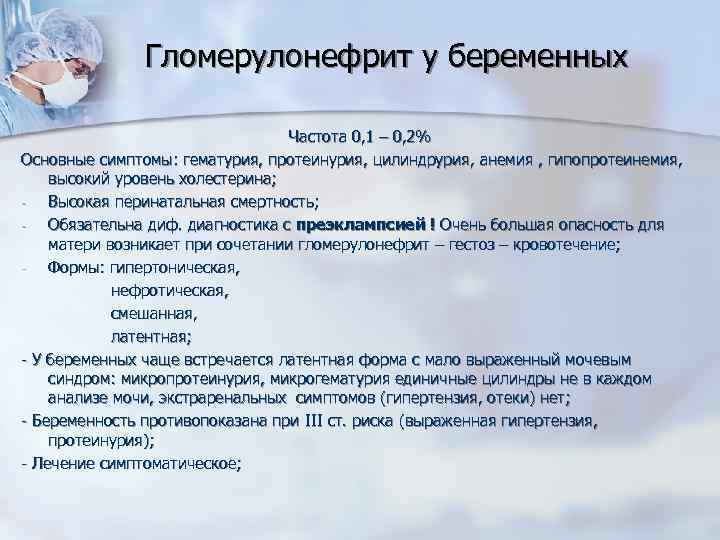

Симптомы подострого гломерулонефрита: фото и описание

Раздел: Визуальный дайджест